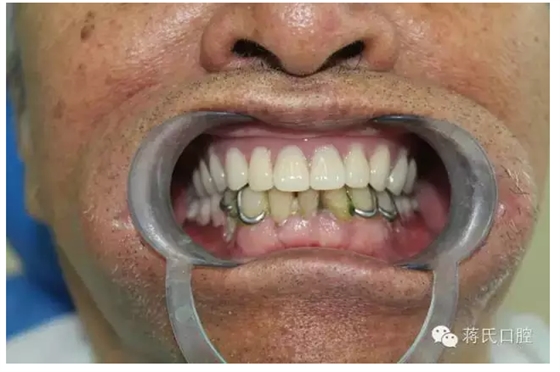

種植醫(yī)師 蔣志剛

修復(fù)廠家 鼎元義齒

主訴 要求修復(fù)缺失牙,因?yàn)樽陨懋愇锔兄?,已于外院修?fù)幾次義齒,均不能使用,要求花費(fèi)最少的錢解決吃飯問題。

5去除上頜基托

6時間 4個月